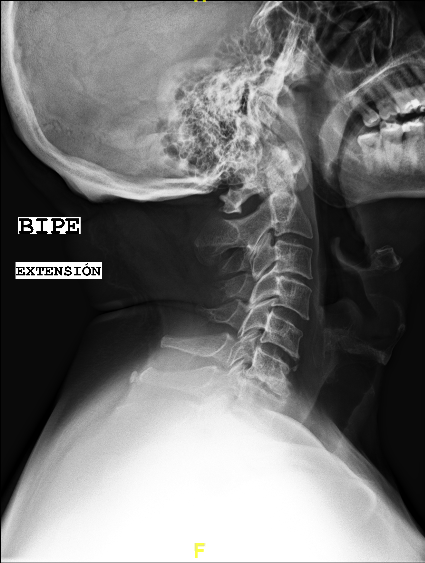

Las RX dinámicas reflejan la ausencia de fusión C6-C7